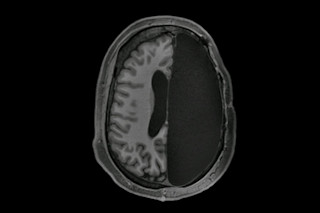

在严重的癫痫病例中,患者的癫痫发作可能变得如此频繁,而且其他治疗方法如此无效,以至于医生会在儿童时期切除一半大脑来阻止它们。这是一种称为半脑切除术的手术。然而,令人难以置信的是,这些患者仍然拥有完整的运动、语言和思维能力。

在一项于周二发表在《Cell Reports》杂志上的研究中,科学家们研究了六名这样的患者,以了解人脑在经历大手术后如何重塑自身以适应。在对患者进行脑部扫描后,研究人员发现,与健康的对照组相比,剩余的半球在不同脑网络——控制行走、说话和记忆等功能的区域——之间形成了更强的连接。

当加州理工学院的认知神经科学家、该研究的首次作者Dorit Kliemann查看一张显示半脑切除术患者功能磁共振成像(fMRI)扫描图的电脑屏幕时,她停了下来。扫描图只显示了一半的大脑——Kliemann惊叹于这些图像来自她几分钟前还在交谈的同一批患者。

Kliemann说,这六名志愿者——他们都在童年时期接受了半脑切除术——现在都是高功能的成年人,语言能力完好。患者的大脑扫描图与大脑正常的人以及来自Brain Genomics Superstruct Project的1500个典型大脑数据库进行了比较。